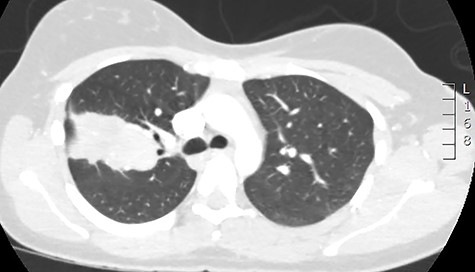

The case was rediscussed at the lung multidisciplinary meeting, and the plan was for the patient to undergo thoracic surgical intervention to remove the mass due to its uncertain nature. As the patient had remained asymptomatic with no haemoptysis and there was no interval change in the mass on surveillance imaging, the patient was brought back for follow-up bronchoscopy. This demonstrated evidence of a previous inflammatory process with cavitation and destruction of sub-lobar bronchial tree. Impression was that the last bronchoscopy had cleared the airway and the patient coughed and cleared the lung distally. The procedure was largely uncomplicated. The patient was subsequently discharged after they had recovered from the anaesthetic. Serial chest radiographs demonstrated almost complete resolution of the right upper lobe mass (Fig. 4). Furthermore, serial IgE titres demonstrated decreasing levels, and this was without the patient being commenced on any antifungal treatment.

Plain chest radiograph demonstrating resolution of the right upper zone mass.